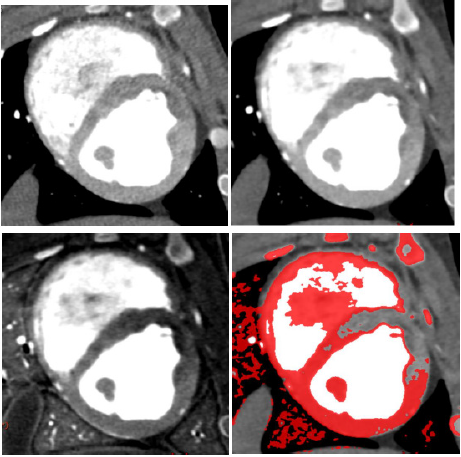

Infarcted Segment Evaluation of S-CCTA and TTC Stain

MI of all the 17 segments according to standardized myocardial segmentation was evaluated by the two points scoring systems. (15) S-CCTA image analysis was performed by using dedicate visual evaluation on optimal energy images. For S-CCTA, score 0 indicated no hypo-perfusion, score 1 represented hypo-perfusion observed. For TTC stain, myocardium in tan color was classified as infarction (score 1) and viable myocardium in red color was regard as score 0 (Figure 1) [16].

The scatterplot showed that 70keV ~75keV were the optimal monochromatic energies to observe infarction region on S-CCTA with higher CNR, SNR and lower noise (Figure 3). 70keV was chosen as the optimal monochromatic energy in our study for the following measurement and comparison. The 70 keV multiplanar reconstruction images could be overlaid with iodine density images; it could provide intuitionistic observation for the location and margin of MI (Figure 4).

Figure 4: A 7-month female pig with acute MI. The anterior and anterior septal hypo-perfusion was demonstrated in A. High voltage B. 70keV C. Iodine density D. 70keV overlay with iodine density images. D depicted the hypo-perfusion more clearly.